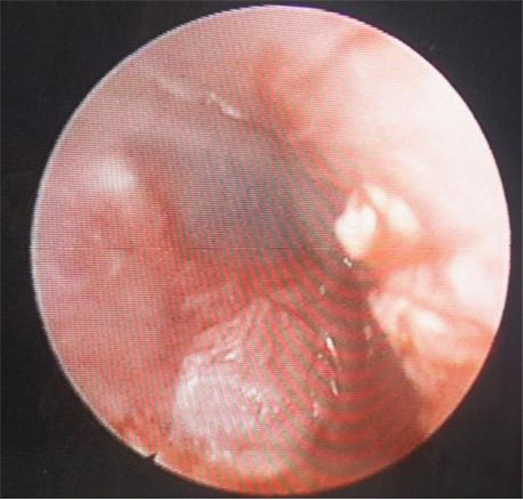

左耳鼓膜穿孔